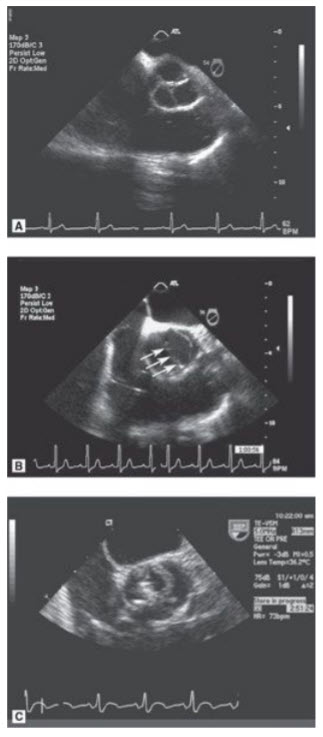

A 36-year-old man with a history of hypertension on medications for 5 years presents to your office with complaints of dyspnea on exertion and is found by his internist to have a heart murmur. Below are some representative views from his TTE (Figs. below A–E).

A. Suprasternal notch view in 2D (TTE). B. Suprasternal notch with color Doppler. C. Continuous-wave Doppler in the descending aorta from the suprasternal notch. D. Parasternal long-axis view in systole. E. Parasternal long-axis view with color Doppler.

Coarctation of the aorta with bicuspid AV with AI. The patient is a young man with hypertension beginning in his late 20s or early 30s. Secondary hypertension must be considered and ruled out in this patient. When he was initially diagnosed he should have had his blood pressure checked in both arms and legs in consideration of a coarctation of the aorta. Note: Someone may also notice rib notching on a chest X-ray. Other etiologies that should have been excluded include renal artery stenosis (more commonly seen in women if caused by fibromuscular dysplasia), pheochromocytoma, Cushing syndrome, or primary aldosteronism. This patient’s heart murmur was a diastolic murmur from AI caused by prolapse of a bicuspid AV. At least 50% of patients with a coarctation have a bicuspid AV. Fewer patients with bicuspid AV have a coarctation. Note that bicuspid AVs dome (doming aortic leaflets are seen in Fig. D in question) and could be mistaken on initial glance in long axis with a rheumatic AV. However, in addition to doming there is prolapse of the conjoined cusp (which would not be seen in a rheumatic valve) and the anatomic situation could be clarified with a good short-axis view.